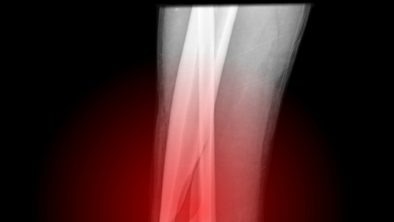

Оскольчатый перелом голени со смещением, лечение перелома голени со смещением

Переломы голени – распространенное в травматологии явление, они могут носить как легкий, так и тяжелый характер, от которого и происходит их классификация. Наиболее сложным считается оскольчатый перелом со смещением. В статье подробно рассматривается характеристика этого вида травм, их классификация и лечение перелома голени со смещением и без. Классификация травм Голень представляет собой структурное соединение из двух трубчатых костей, мышц, сосудов, нервной ткани и соединительных элементов в нижней части конечности между коленным суставом и стопой...